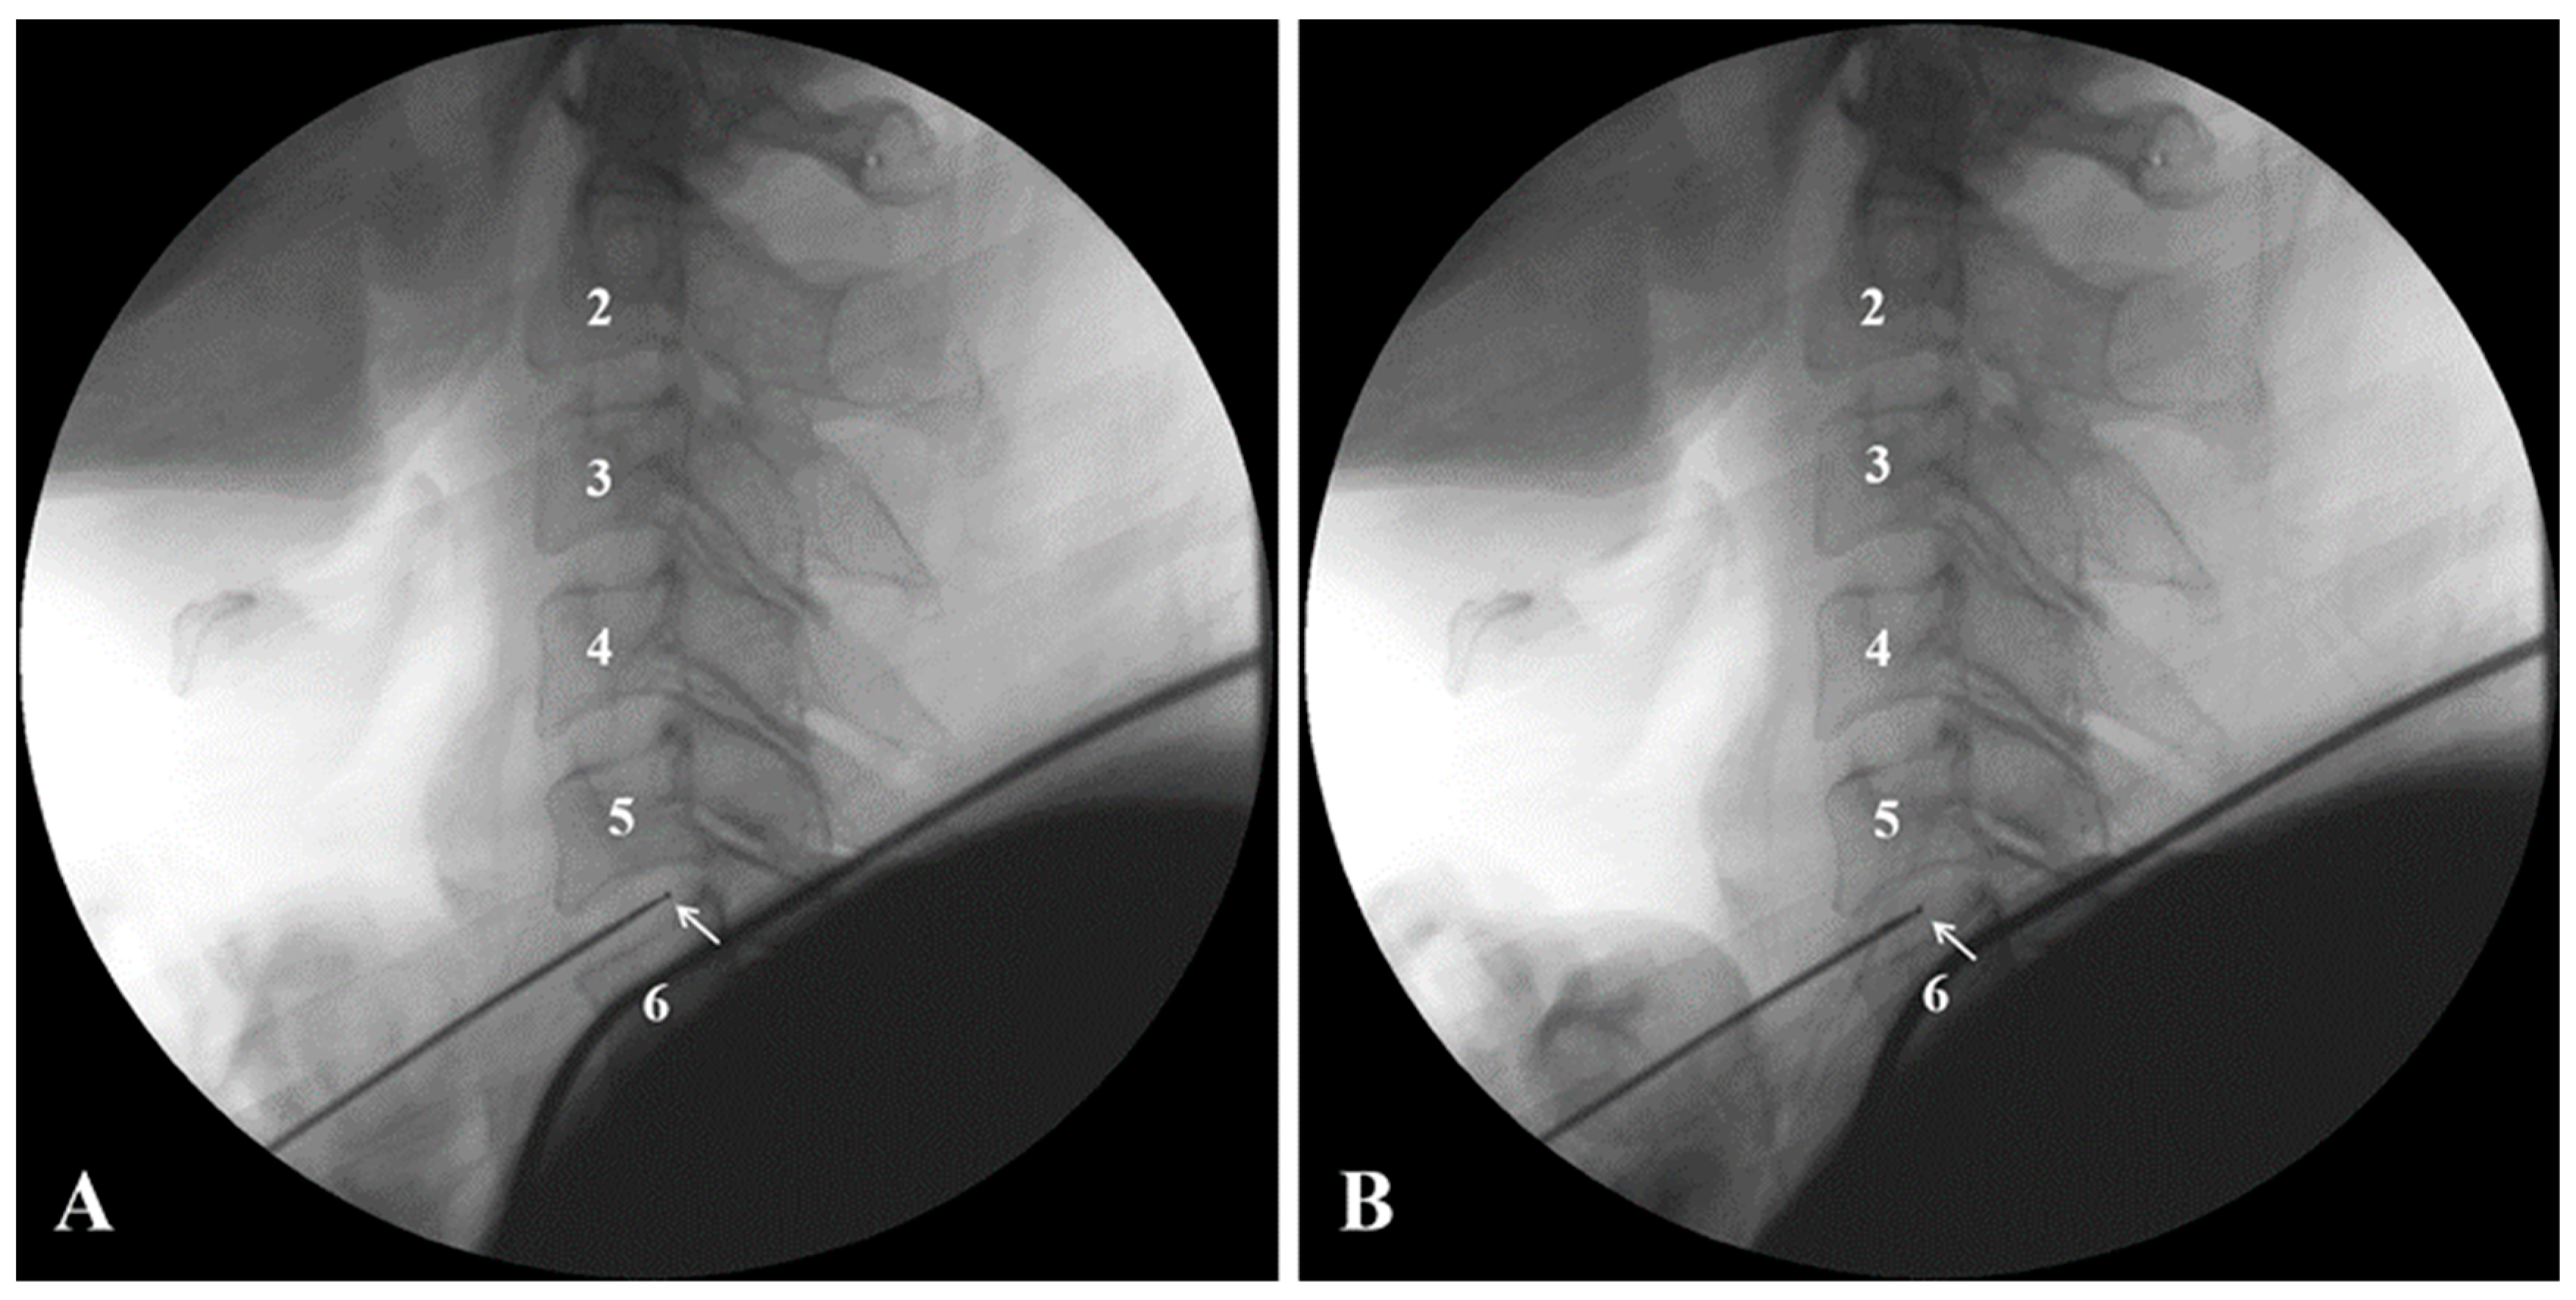

2.2. Cervical Coblation Nucleoplasty